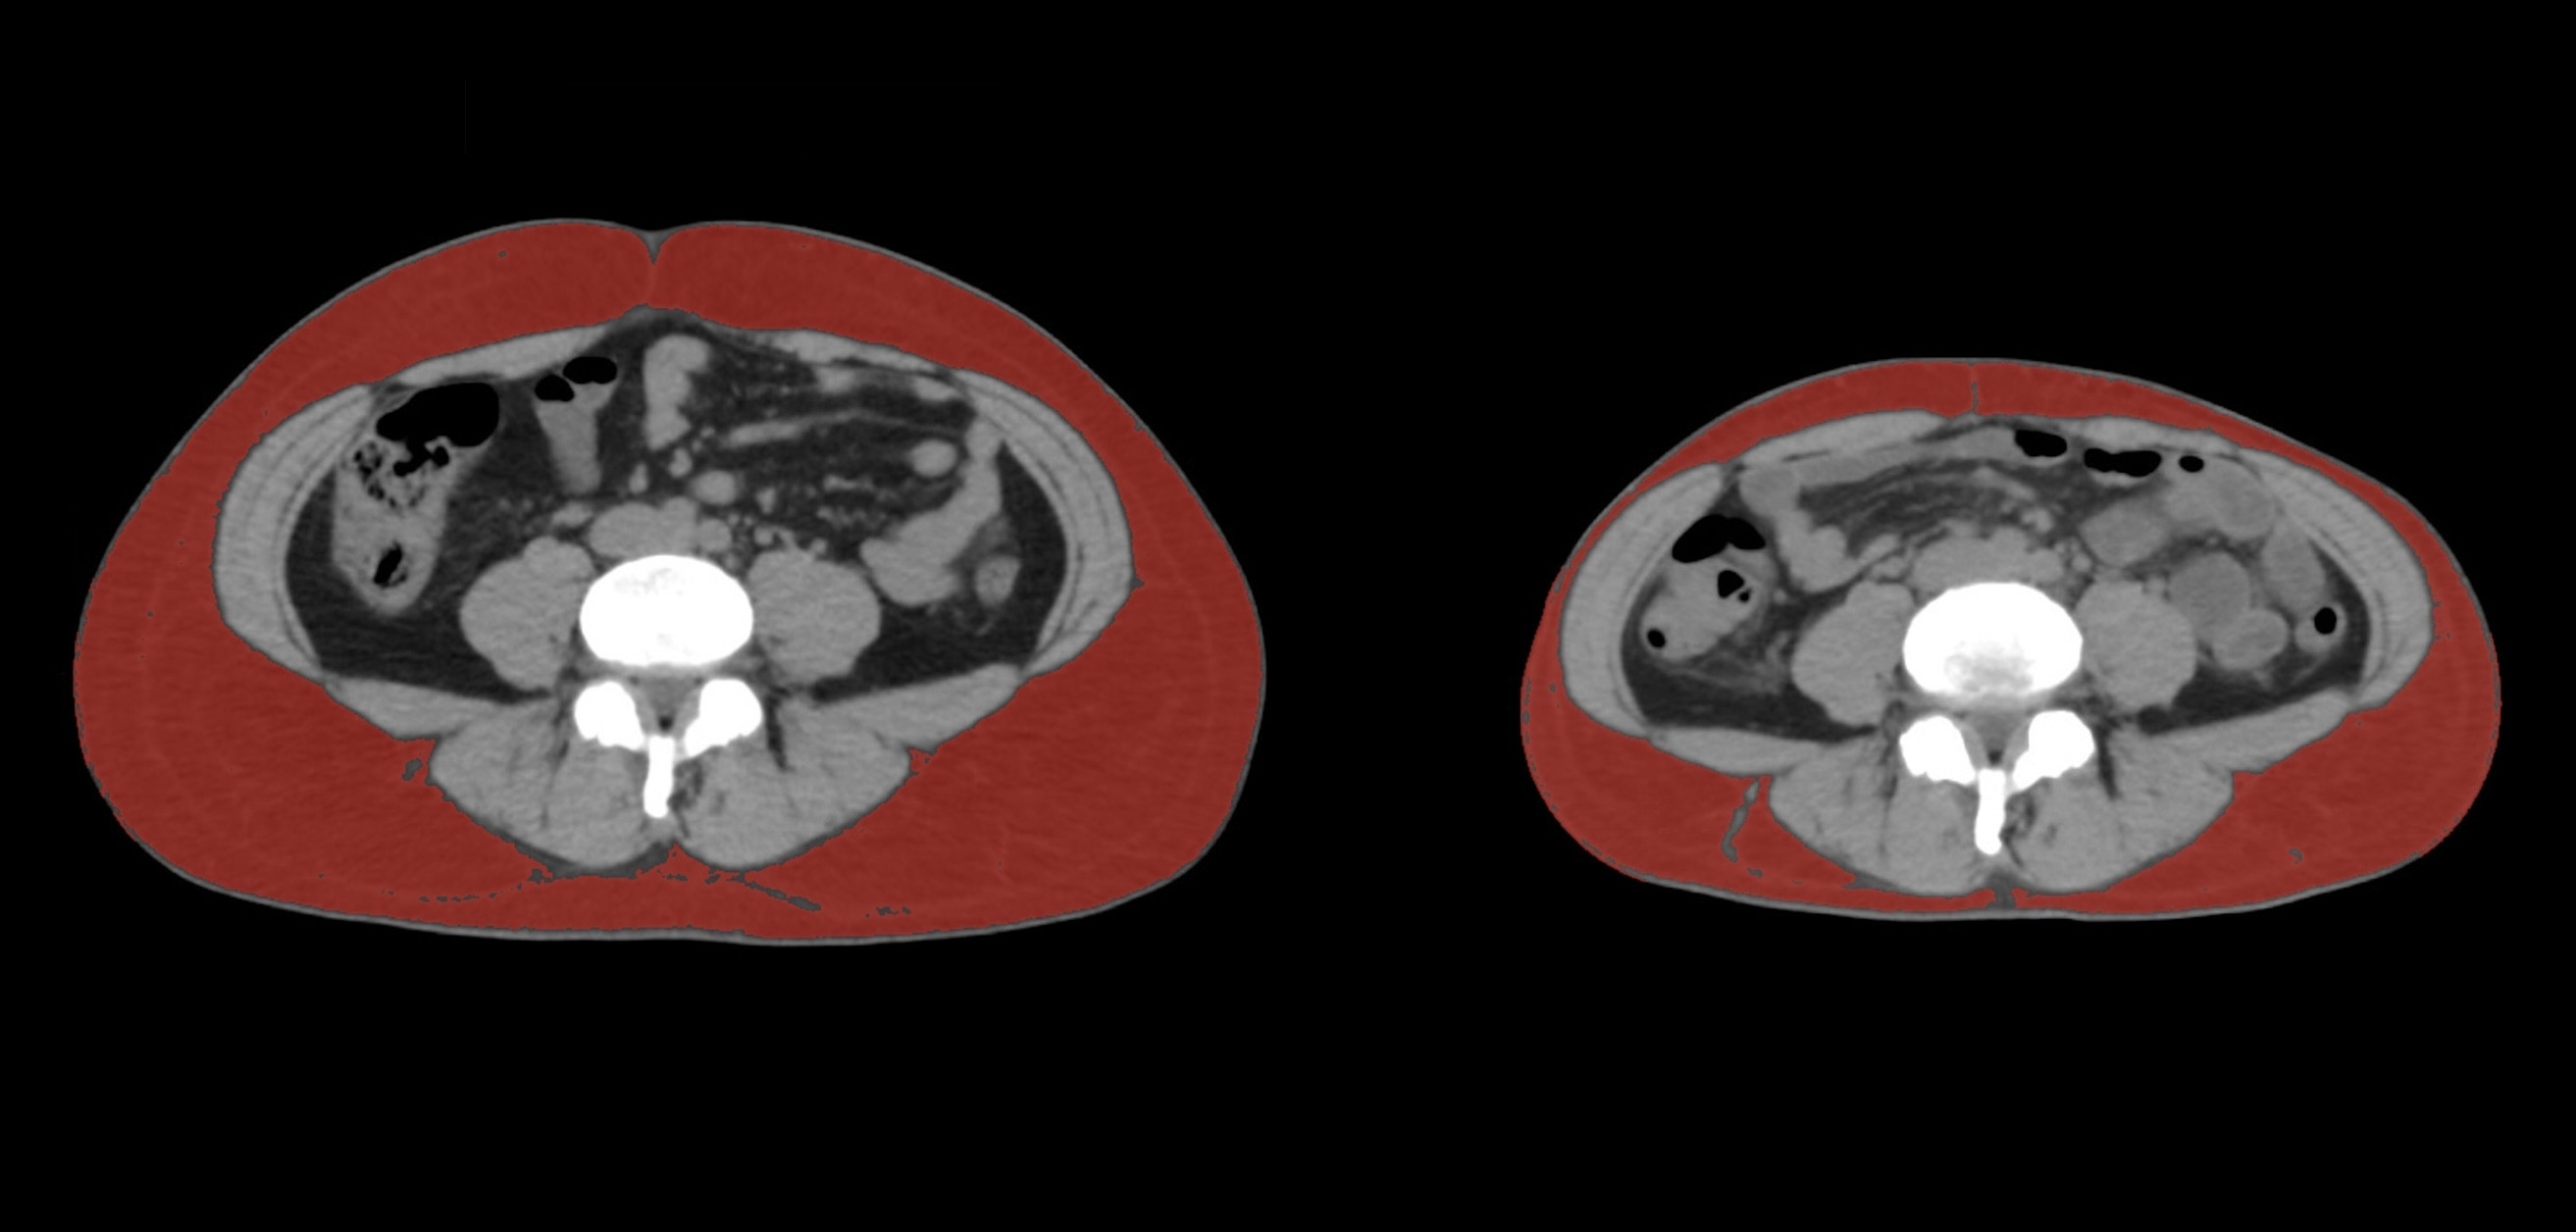

③

50代・男性(ご本人のご厚意で画像提供)

治療内容:チルゼパチド5.0mgの週1回自己注射による脂肪減少と脂肪肝改善

治療期間: 6ヶ月(26週)((用量は2.5mgから開始し最大で15mg。減量効果が得られる必要用量には個人差があります。))

費用:自由診療の場合は7700円(税込)×26(週)=200200円

想定されるリスク・副作用:下記に副作用を記載

※医療広告ガイドラインに準拠して表記

1:脂肪の減少

皮下脂肪の減少(赤色部分)